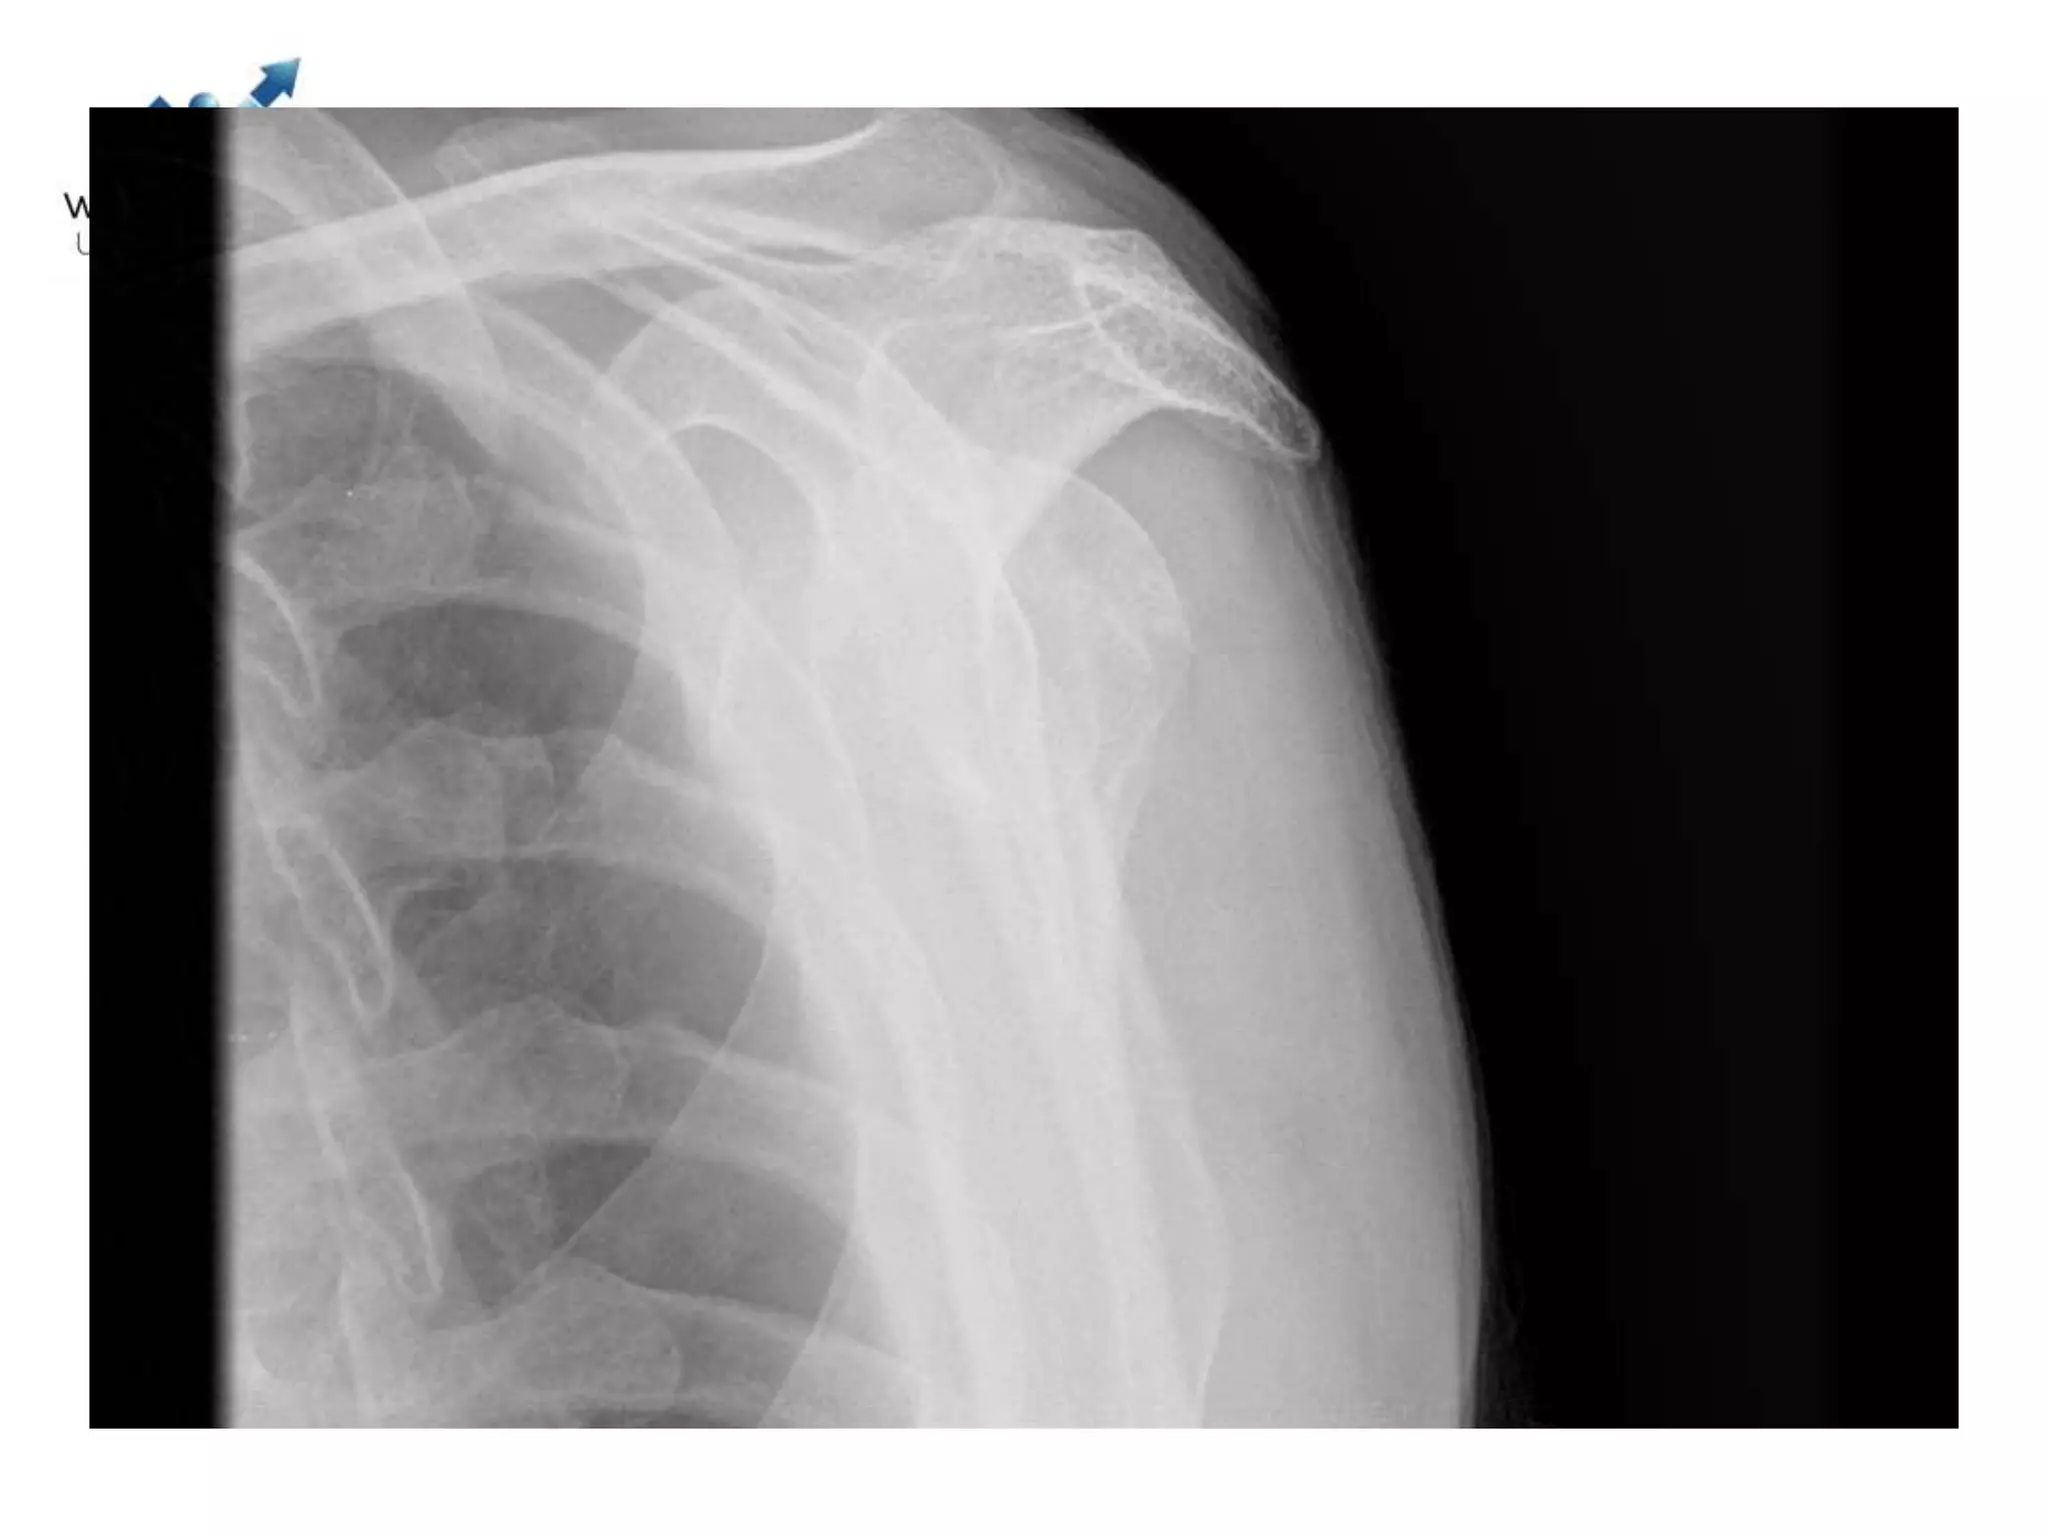

• Majority Non-operative (Appx 85%)

Case discussions